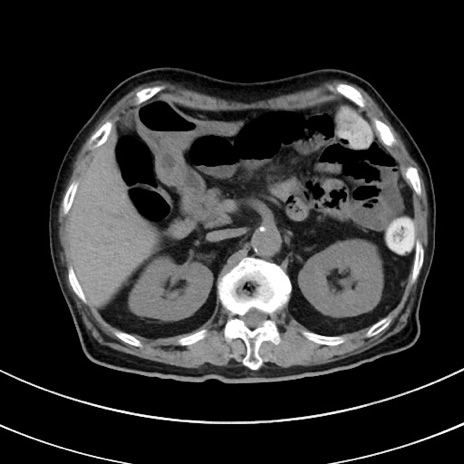

症例33(横断像)

【症例】70歳代 女性

【主訴】心窩部痛

【現病歴】延髄病変の精査・加療にて神経内科入院中。本日より心窩部痛あり。

【既往歴】虫垂炎

【身体所見】右下腹部を中心に圧痛と反跳痛あり。

【データ】WBC 10900、CRP 0.02